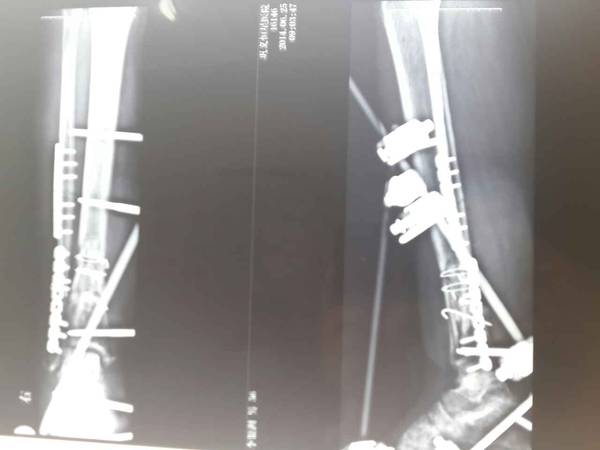

上传术后X线片